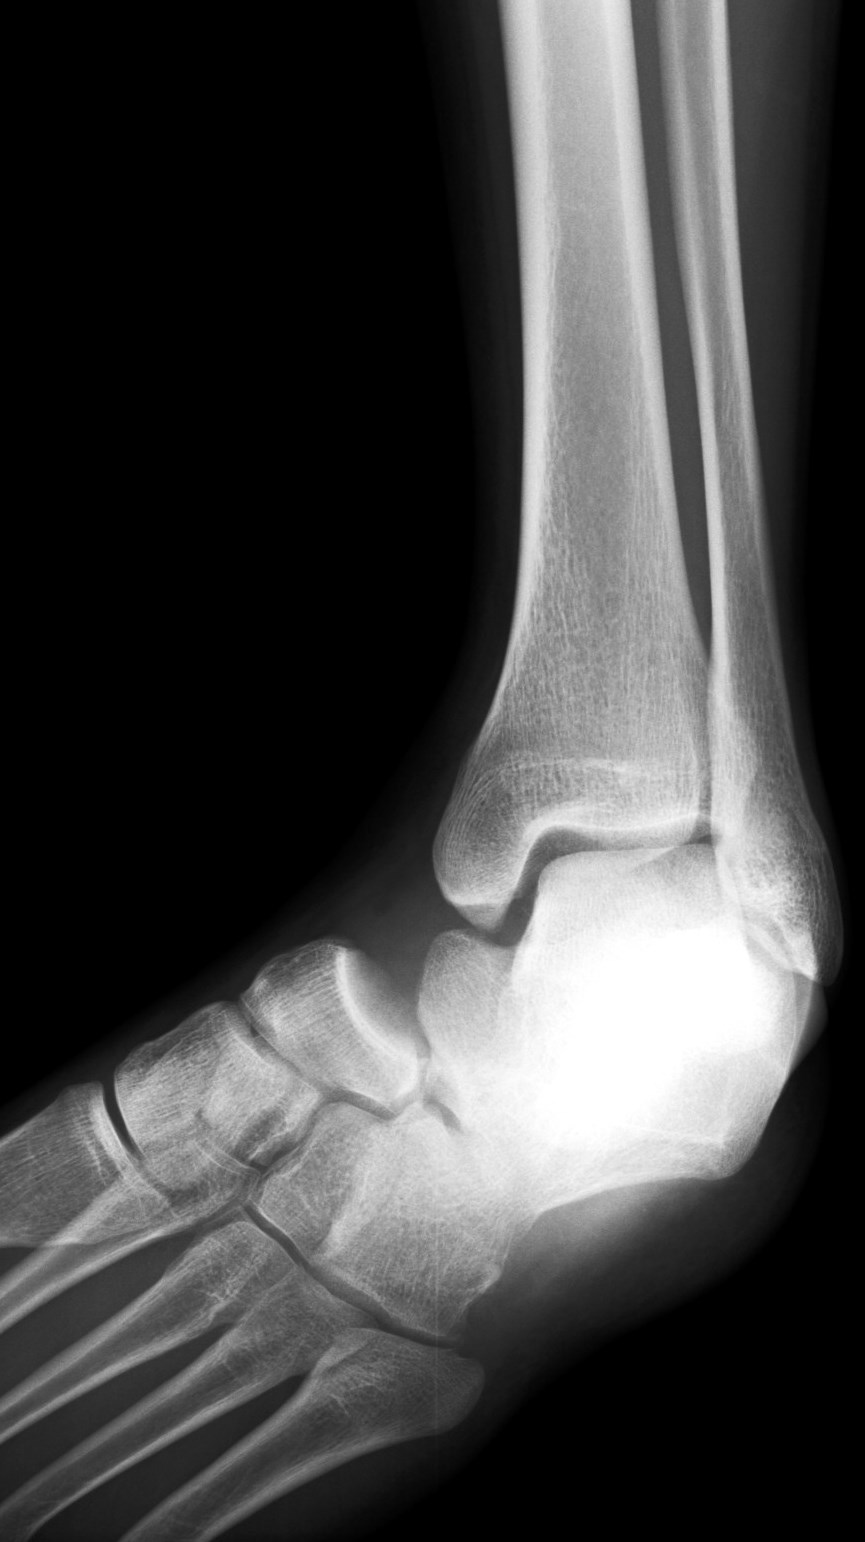

16 y/o s/p skateboard injury. Severe pain.

Medial subtalar dislocation. The photo is a representation, not this actual patient. 80% are medial like this. Trauma to an inverted plantar flexed ankle. Reference article.

Medial subtalar joint dislocation( RID3029 )